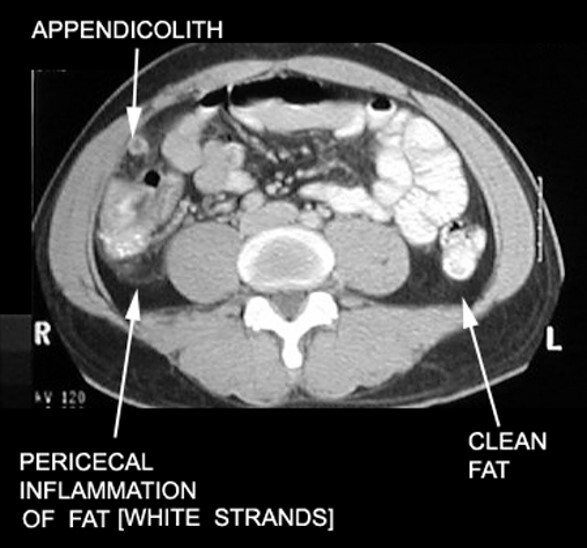

10

Q

A

-fat stranding

-inflammation extending up distal cecum

-fat in that area